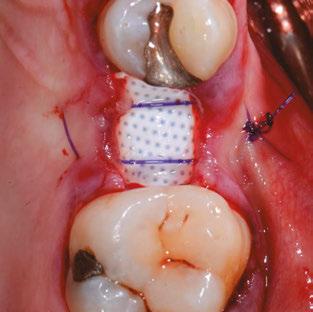

Building on the basics

Let’s review a recent case that showcases the rationale and techniques of the top three. It is common to utilize several suturing techniques in surgical closure, especially in larger grafting cases. In the following case, a lateral sinus lift was performed, and all three techniques were used to their full effect. Simple interrupted sutures are used to close small incisions and place tissue margins accurately back in place; horizontal mattress sutures are used to hold membranes in place and relieve tension over the incision line, and running interlocking continuous sutures are used to close longer incisions with watertight closure for maximum healing potential via primary closure.

Figures 7A and 7B: Horizontal mattress sutures are useful for helping to secure membranes in grafting situations and relieving tension in longer span incisions Figures 8A and 8B: The pre-op condition of the patient with mini implants engaging minimal bone and perforating the sinus. The patient’s implant supported bridge was loose and causing discomfort Figure 9: A periosteal biting mattress engages only the periosteum in the buccal vestibule and exit and re-enters on the lingual tissue, helping to secure the membrane tightly over the window and crest